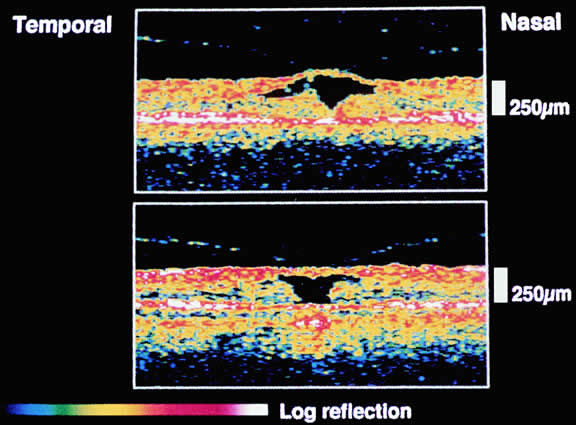

Recent OCT studies suggest a different interpretation of the biomicroscopic findings of macular hole formation.87,88 OCT is capable of imaging the status of the posterior vitreous cortex during macular hole formation. OCT demonstrates that the first event in macular hole formation is a perifoveal detachment of the posterior vitreous cortex with persistent adherence of the posterior vitreous cortex to the foveal center resulting in vitreous traction on the foveal center. In this scheme, stage 1-A hole is the result of an intraretinal split or pseudocyst between the inner retina consisting of bipolar and ganglion cells and the outer retina consisting of the Henle fiber layer and outer nuclear layer. The foveal pseudocyst results in foveal thickening and the characteristic biomicroscopic appearance of a stage 1-A macular hole.

OCT demonstrates that in stage 1-B macular hole the pseudocyst extends posteriorly disrupting the outer retinal layers at the foveolar center. The yellow ring of the 1-B hole is thought to represent edema of retinal tissue adjacent to the central foveolar dehiscence. The xanthophyll pigment is displaced more peripherally and based on blue filter photographs is not thought to be related to the characteristic yellow ring (Fig. 15).

Fig. 15. Top. shows the center of the fovea thickened by a cystic space. The posterior hyaloid adheres to the roof of the cyst. Bottom. A large central cystic space formed by a ventral opening in the photoreceptor layer.

OCT confirms the complete detachment of the prefoveal vitreous cortex, intraretinal thickening resulting from cystic spaces, and elevation of the retina from the pigment epithelium surrounding the macular hole87,91 (Fig. 18).

Fig. 18. Stage 3 hole. Top. Optical coherence tomogram (3 mm long) shows the hyperreflective operculum (arrow) next to the minimally reflective membrane corresponding to the posterior hyaloid. The edges of the hole are thickened by cystic spaces and detached from the retinal pigment epithelium by 850 μm (arrowheads). Bottom. Composite optical coherence tomogram shows the detachment of the posterior hyaloid from the entire posterior hole. (OD, optic disc).